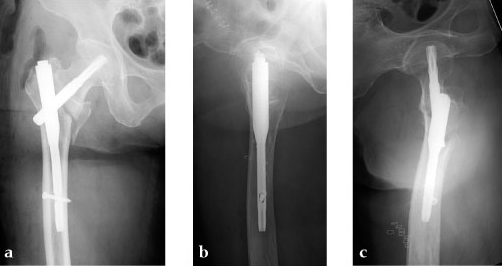

Case 4: 77-year-old male.

Case provided by Takeshi Sawaguchi, Toyama, JP

78-year-old female.